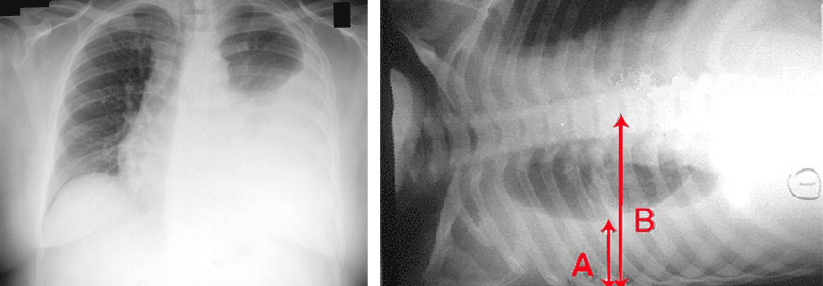

Um das Ausmaß eines malignen Pleuraergusses rasch abzuschätzen, braucht es zunächst keinen Röntgenthorax. Eine einfache Bewegung liefert objektive Anhaltspunkte.

Dieser einfache Test erlaubt es, Rückschlüsse auf das Ausmaß des Pleuraergusses zu ziehen, so Prof. Lee. Je größer der Erguss im Röntgenthorax, desto kürzer war die Toleranzzeit. Nach Drainage von median 1,3 Litern Flüssigkeit verbesserte sie sich, viele Patientinnen und Patienten konnten dann ohne Atemprobleme eine Minute lang die beschriebene Haltung beibehalten. Eine Bendopnoe war zudem mit einer insgesamt ausgeprägteren Atemnot und schlechteren Ergebnissen im Sechs-Minuten-Gehtest assoziiert.